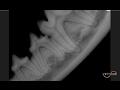

Dental Radiography

01/31/2017

Daniel Carmichael, DVM, FAVD, DAVDC discusses principles of veterinary dental radiography and provides case-based learning on dental radiography in companion animals. Learn more on dentistry topi...